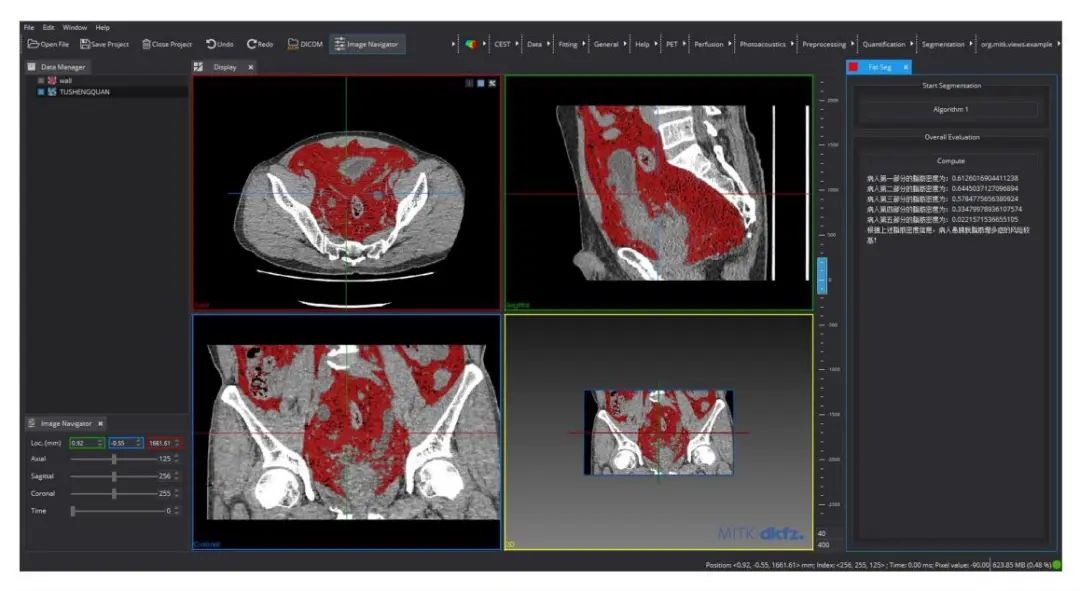

未来技术学院岳晓冬教授团队的“基于‘数据+知识’深度学习的泌尿疾病影像分析系统”聚焦智能辅助诊断中的模型可解释性与领域知识融合问题��,创新性地提出“数据+知识”的深度学习方法����,将专家决策规则有效嵌入深度神经网络���,提升模型解释性与系统自主决策的可靠性��,实现更高水平的人机协同���。

泌尿疾病影像分析系统